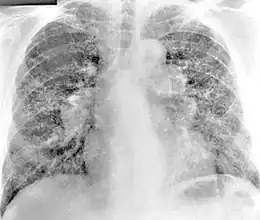

La bérylliose (CBD, pour l'anglais chronic beryllium disease) est une maladie induite par l'exposition au béryllium ou à ses composés. C'est une pneumoconiose donnant une pneumopathie interstitielle diffuse à l'imagerie médicale[1]. Sa fréquence est certainement très sous-estimée, faute d'identifier la plupart des expositions au béryllium[2].

- il est toxique et source de bérylliose chronique (« granulomatose multisystémique à tropisme pulmonaire largement prédominant ») ; Cette granulomatose immunologique, a un tableau clinique qui évoque une sarcoïdose ou une fibrose interstitielle diffuse idiopathique[2] ;

Après une exposition unique ou prolongée par inhalation, les poumons développent une hypersensibilité au béryllium, à l'origine du développement de nodules inflammatoires, les granulomes.

Des granulomes sont retrouvés dans d'autres maladies chroniques, comme la tuberculose, la sarcoïdose. Il est pour cette raison parfois difficile de distinguer la bérylliose de ces affections.

À terme, ce processus conduit à une atteinte pulmonaire restrictive, avec une diminution de la capacité de diffusion.